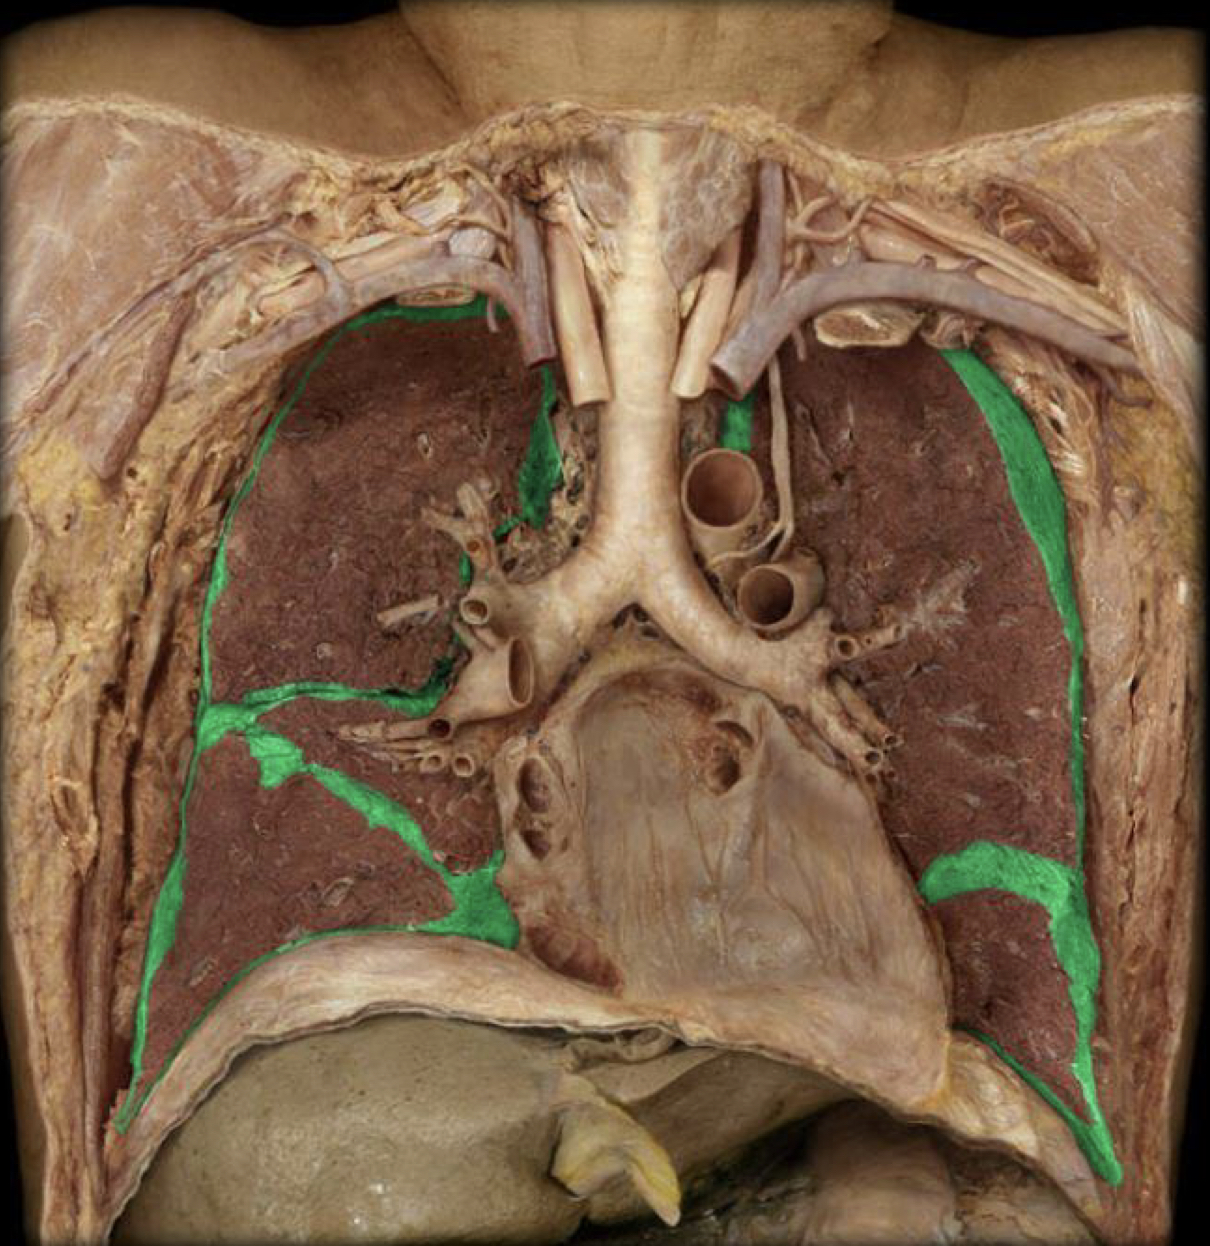

What structure is highlighted in green?

Visceral pleura

New cards

Parietal pleura